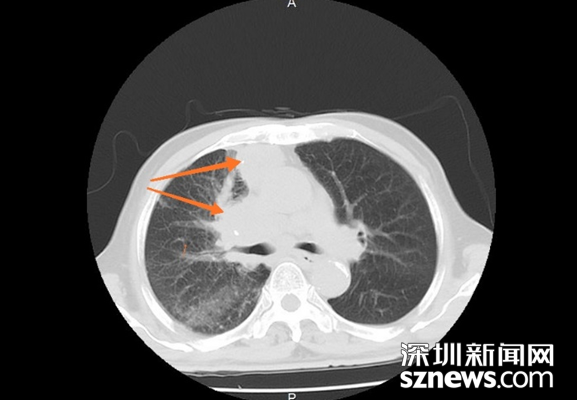

低剂量CT筛查发现右肺肿物

深圳新闻网2019年2月20日讯(记者 刘梦婷 通讯员 刘晓韵 刘迪敏 张伟)深圳光明区的李大爷今年78岁,年年体检的他身体也一直不错。可是从去年11月底起,李大爷开始不停地咳嗽咳痰,起初老人以为是感冒。随着时间推移,老人家的病症越来越重,来到中山七院就诊,做了胸部CT检查后发现是肺癌。

李大爷在子女的陪同下来到中山七院胸外科复诊。通过进一步检查,确诊为右肺癌并胸膜转移,纵膈、腹膜后淋巴结转移。这一消息仿佛晴天霹雳,让全家人不敢相信。